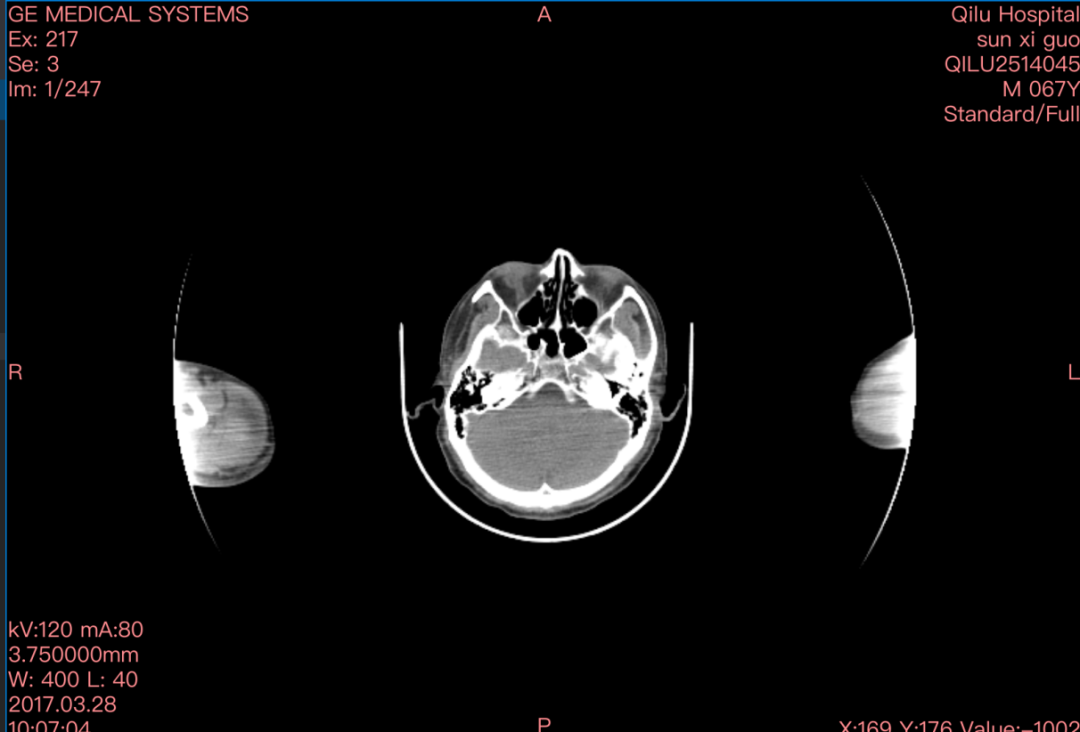

“影像组学”,我们把它们拆成“影像”和“组学”两个词来说。这里的“影像”通常指的就是放射影像,是这种方法研究的对象,目前大家选择最多的是CT、MR等影像。组学,英文为Omics,想必作为生信人的大家一点都不陌生吧,是目前生物和医药前沿研究领域最流行的后缀了,是高通量数据的代名词。所以,影像组学的研究对象是医学影像,研究方法是将影像中的所有信息提取出来再进行系统化分析,确切来说,影像组学是采用自动化算法从影像的感兴趣区(ROI)内提取出大量的特征信息作为研究对象,并进一步采用多样化的统计分析和数据挖掘方法,从大批量信息中提取和剥离出真正起作用的关键信息,最终用于疾病的辅助诊断、分类或分级。

听到这里,大家是不是有些熟悉呢,没错,其实从医学影像中提取出来的数据形式和我们的单细胞数据十分的类似,一张影像可能对应着上千条特征,所以所谓“组学”,真的名副其实。今天给大家手把手教学如何从医学影像中提取影像特征,感兴趣的小伙伴快来跟我一起实战练习吧。特别提示,本次操作需要通过Python进行,并且对电脑配置有一定需求,建议大家使用服务器运行,如果没有自己的服务器欢迎联系我们来租赁服务器哦~